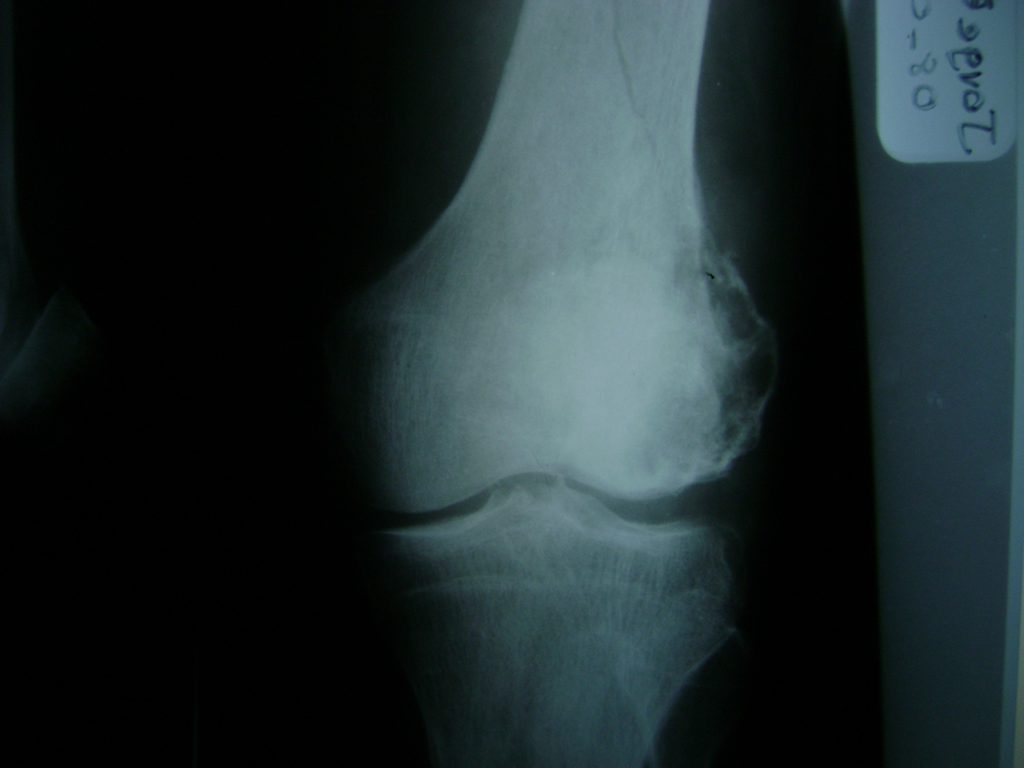

La artroscopia de rodilla es un cirugía en el cual la estructura interna de la articulación es examinada ya sea para realizar un diagnostico o para realizar un tratamiento, este procedimiento se realiza utilizando un instrumento parecido a un pequeño tubo llamado artroscopio.